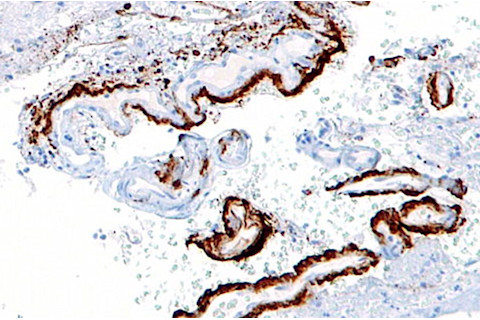

In 1982, Nobel prize-winner Stanley Prusiner first discovered prions—misfolded proteins that act as infectious agents, spreading the disease within and among individuals. Two years later, he speculated that Alzheimer’s disease might involve a similar spread of malformed proteins, at least within patients. Recent experiments have supported his idea. [The hallmarks of Alzheimer’s] include tangled clumps of amyloid-beta, a peptide (protein fragment) that aggregates in large plaques. Lary Walker from Emory University and Mathias Jucker from the University of Tübingen managed to trigger the spread of amyloid-beta plaques in the brains of mice by injecting them with brain extractsalready containing clumps of the peptide. But these extracts always contained other proteins that could have been responsible for the spread of the plaques. Now, Prusiner, along with Jan Stohr and Joel Watts from University of California, San Francisco, have shown that pure amyloid-beta can achieve the same effect on its own.